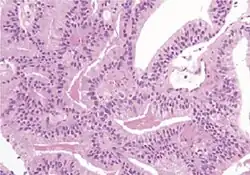

Acinar adenocarcinoma

These constitute 93% of prostate cancers.[2]

Microscopic characteristics

- Specific but relatively rare

- [notes 4]

- Collagenous micronodules[4]

- Glomerulations,[4] epithelial proliferations into one or more gland lumina, typically a cribriform tuft with a single attachment to the gland wall.[18]

- Perineural invasion.[4] It should be circumferential[18][notes 5]

- Angiolymphatic invasion[4]

- Extraprostatic extension [4]

- Relatively common and highly specific

- [4]

- Multiple nucleoli

- Eccentric nucleoli[4]

- Less specific findings.

- Mitoses (also seen in for example high-grade prostatic intraepithelial neoplasia (HGPIN) and prostate inflammation).[4]

- Prominent nucleoli[4]

- Intraluminal eosinophilic secretion[4]

- Intraluminal blue mucin[4]